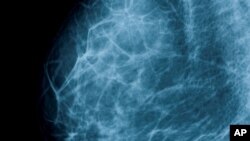

Нова студија за ефективноста на мамографија со рентгенски зраци, што се користи при скенирање за рак на дојка кај жените, најде дека мамограмите резултирале во мал процент намалување на смртноста од болеста.

Студијата опфатила околу 40 илјади норвешки жени, на возраст меѓу 50 и 69 години, кои беа дел од програмата за скенирање на рак на дојка. Како дополнение на нивното учество во програмата, жените биле подложени на мамографија секои две години, меѓу 1996 и 2005.

Нивните резултати биле споредени со жени во други држави кои исто така биле дел од програма за менаџмент и едукација за рак на дојка, но немале мамограми.

Истражувачите нашле дека групата подложена на мамографија имале само десет проценти намален ризик од смрт од рак на дојка споредено со жените кои не биле на рентгенско снимање.